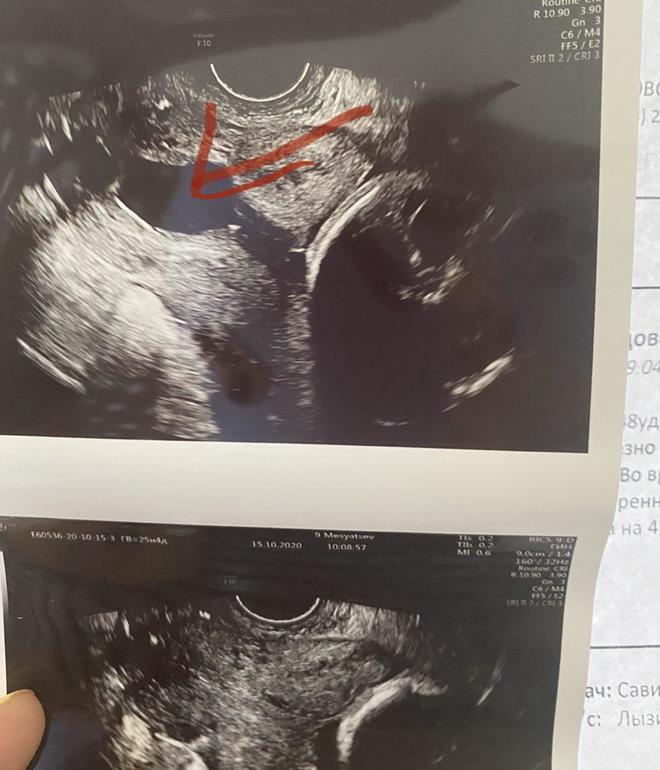

сначала все было закрыто и все гуд, потом резко на мониторе смотрю, и внутренний зев мой воронкой который резко открывается , а в средней части вообще открылось до 23 мм (вот фото) посередине как раз где стрелкой отмечено, открывается аж до самых швов...

вот отметила красным где швы...белые точки

какое-то открытие было, возможно.. или хз...

сказали что лентой да.. но я хз... ленту видно на узи как 2 белые точки по бокам ( в комменте выше отметила на фото красным свои швы)